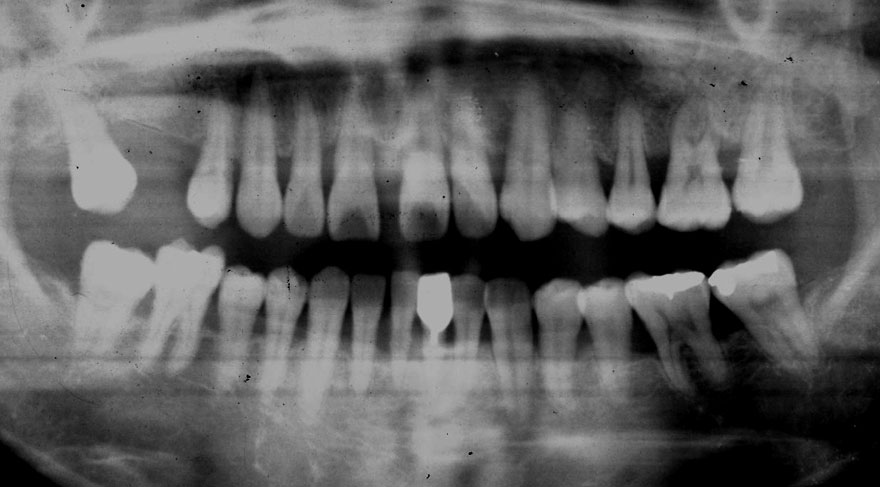

初診時 45歳 女性 平均歯槽骨喪失量:1.94mm

26年後 71歳

平均歯槽骨喪失量:2.16mm

26年間喪失量:-0.22mm

年間喪失速度:-0.008mm

(ケア頻度:1.56ヵ月ごと)